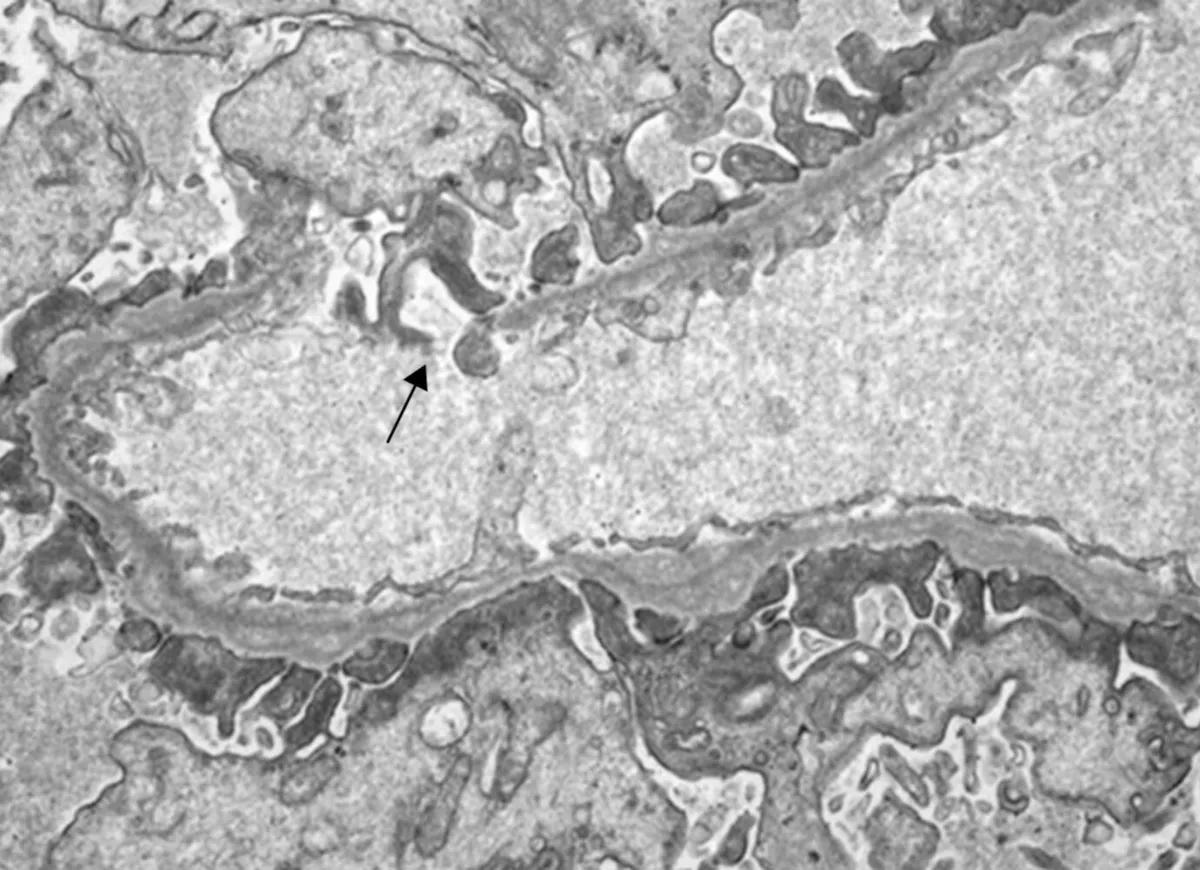

Injúria Renal Aguda (revisão Lancet 2025)

Injúria Renal Aguda (revisão Lancet 2025)